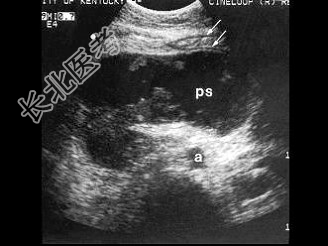

- [材料题] 女性患者,56岁,急性胰腺炎1周。B超图像如图。

- 简答题1、请问该病例诊断为?